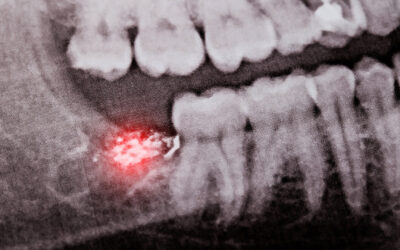

Why You May Need Your Wisdom Teeth Removed

Wisdom teeth, or third molars, are the last adult teeth to develop and erupt. For many people, these teeth do not have adequate room to come in properly,...